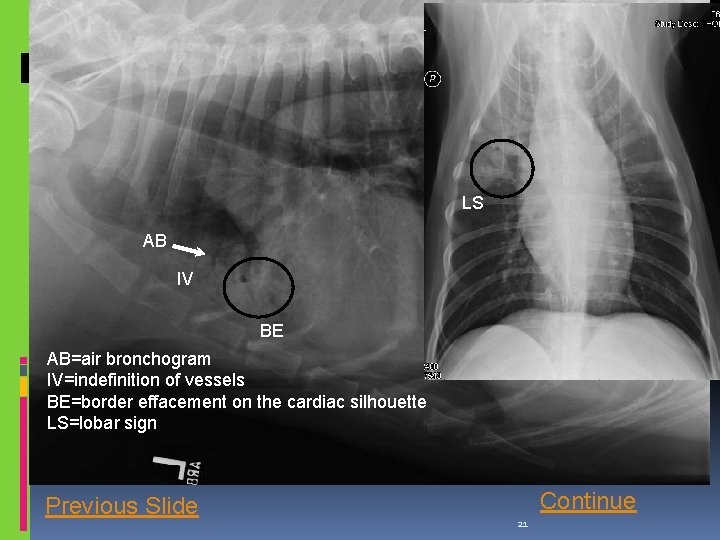

Correct! This is an example of an alveolar pulmonary pattern. Some of the features of this pattern include: Indefinition of the pulmonary vessels, air bronchograms, lobar sign, and (in this case, discrete) border effacement of the lobar opacification with the cardiac silhouette. Remember: It does not have to have all these features to be considered an alveolar pattern! Continue

LS AB IV BE AB=air bronchogram IV=indefinition of vessels BE=border effacement on the cardiac silhouette LS=lobar sign Previous Slide Continue 21

Conclusion Your findings now include: increased soft tissue pulmonary opacity within the right cranial lung lobe, with presence of indefinition of the pulmonary vessels, air bronchograms, lobar sign, and (in this case, discrete) border effacement of the lobar opacification with the cardiac silhouette. This represents an alveolar pulmonary pattern, which, in this case, is mainly ventral. click next.